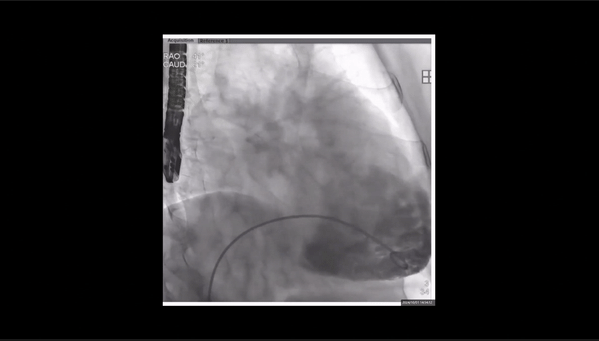

術(shù)后即刻返流

術(shù)后即刻返流三維

瓣膜釋放

術(shù)前術(shù)后返流情況對比